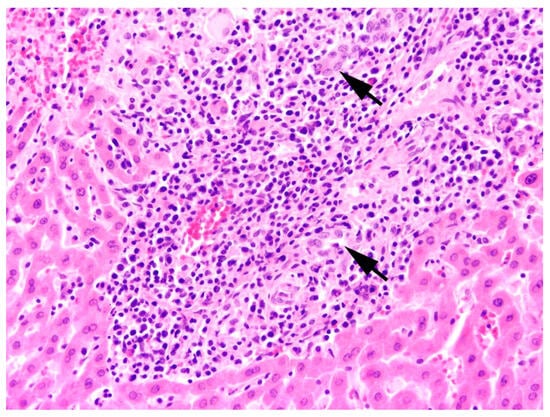

The main type of hepatitis was non-purulent with different proportions of lymphocytes, plasma cells, and macrophages (93.0%, n = 80; Figure 4), followed by purulent (14.0%, n = 12), necrotising (5.8%, n = 5), and granulomatous type (5.8%, n = 5). Eight cases (9.3%) of hepatitis showed a mixed inflammatory type.

All inflammations of the kidneys were non-purulent, with interstitial infiltrations of lymphocytes, macrophages, and plasma cells (Figure 12). In one adult male, fibrosis and depression on the kidney surface were observed.

Typical pathomorphological alterations such as hepatocellular necrosis were diagnosed in seven (10.4%) lagovirus seropositive animals, mainly including animals sampled from Friedrichskoog (n = 6) and adults (n = 5). Six mainly adult animals (n = 5) with pathognomonic hepatocellular necrosis could not be tested for lagovirus infection. Furthermore, hepatitis was correlated with certain EBHSV infections (n = 29), uncertain EBHSV or RHDV2 infections (n = 4), and not further determinable lagovirus infections (n = 2). Following previous studies on EBHSV [30,49], a suspected chronic or subclinical form with mild lymphocytic hepatitis was detected in 53.3% (n = 32) of EBHSV-seropositive cases (RT ≥ 4), including nine hares with recent to very recent infection.